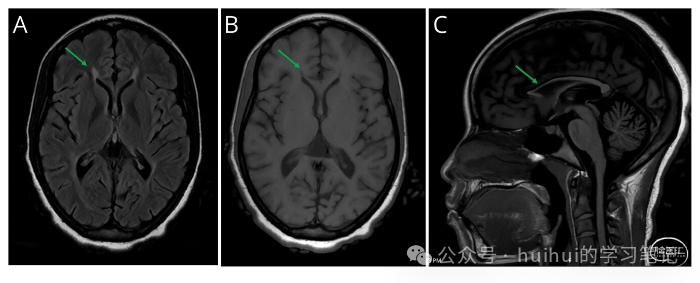

我们通过血液检查寻找慢性脊髓病的病因,神经轴的MRI检查评估结构改变,CSF检查寻找炎症,肌电图/神经传导研究(EMG/NCSs)评估神经病变。维生素B12、甲基丙二酸、铜和维生素E水平正常。HTLV I/II、HIV和梅毒血清学均为阴性。脑MRI显示胼胝体变薄,胼胝体压部可见T2/液体衰减反转恢复(FLAIR)高信号和T1低信号(图)。脊柱MRI无明显异常。脑脊液检查显示白细胞2个/μL(正常,<5个/μL),蛋白45 mg/dL(正常,≤45 mg/dL),葡萄糖正常,IgG指数正常,无CSF特异性寡克隆带(正常,<2)。EMG/NCS 正常。

头部MRI轴向FLAIR (A)和T1 (B)序列显示山猫耳征象(胼胝体压部FLAIR高信号和T1低信号),矢状T1 (C)显示胼胝体薄。FLAIR =流体衰减反演恢复。

这些结果没有指向结构性、代谢性、感染性、脱髓鞘/炎症性和肿瘤性脊髓病。EMG/NCS 也没有神经病变的证据。在胼胝体压部(图)上发现 T2/FLAIR 高信号和 T1 低信号异常是特征性的,被称为“猞猁耳征”。这一发现,除了提示胼胝体压部变薄外,还高度提示了最常见的“复杂”HSP 类型与相关的薄胼胝体 (SPG11 和 SPG15)。因此,我们决定进行基因检测。

SPG11 是最常见的常染色体隐性遗传 HSP 亚型,占 HSP 病例的 8%。症状通常发生在 4 至 36 岁之间,与 HSP 相比,它总是具有“复杂”表型,而 HSP 的特征是仅累及长束。大多数病例最初表现为认知障碍,然后是下肢痉挛,通常在生命的第二个十年(就像我们的病人一样)。其他特征可能包括轴索运动神经病(SPG11 是肌萎缩侧索硬化症 5 和 Kjellin 综合征的等位基因),帕金森综合征、共济失调、癫痫发作和黄斑病变。典型的影像学检查结果是薄胼胝体和“猞猁耳”征(敏感性 78%-97%,特异性 90%-100%)。治疗包括遗传咨询的持续支持、转诊至痉挛性截瘫基金会 (SPASTIC Paraplegia Foundation, sp-foundation.com) 和纵向多学科管理,包括持续的神经系统护理、物理治疗和症状管理(例如痉挛状态和膀胱功能障碍)。